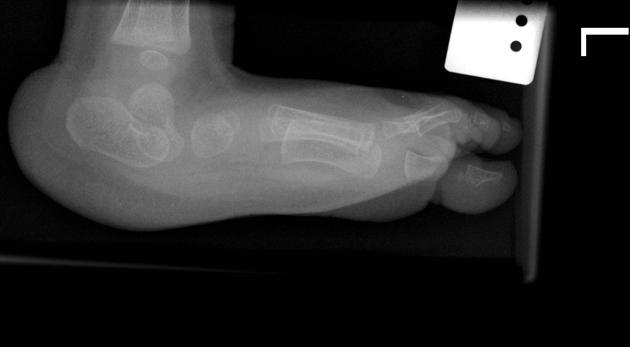

Metatarsus adductus

hindfoot is fine in this one, they usually self resolve

MC than clubfoot